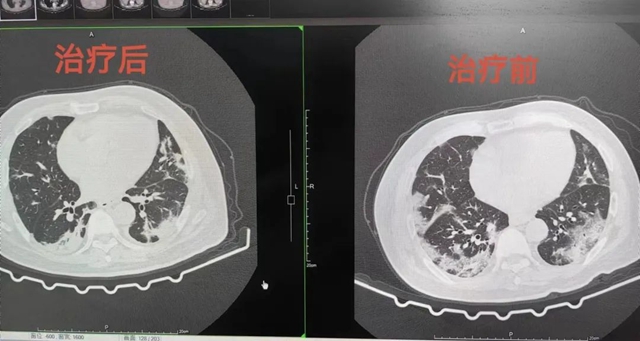

疼痛科韩聪主治医师接诊后,立即为黄大爷安排了相关检查,结果胸部CT提示双肺散在多发炎症,核酸检测也呈阳性。

韩聪回忆说:“当时他情况很差,从胸部CT片子上看,肺部很多地方都花白了,我们立即为其办理了入院,并下达了病危诊断,随时准备转入ICU进行重症监护。”

通过中西医结合治疗,黄大爷的情况日益好转,之前预订的ICU病床都没用上,半个月后便康复出院,出院时还送来了三面锦旗表示感谢。